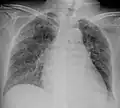

Chest X ray showing miliary tuberculosis

Miliary tuberculosis is a form of tuberculosis that is characterized by a wide dissemination into the human body and by the tiny size of the lesions (1–5 mm). Its name comes from a distinctive pattern seen on a chest radiograph of many tiny spots distributed throughout the lung fields with the appearance similar to millet seeds—thus the term "miliary" tuberculosis. Miliary TB may infect any number of organs, including the lungs, liver, and spleen.[2]

Testing for miliary tuberculosis is conducted in a similar manner as for other forms of tuberculosis, although a number of tests must be conducted on a patient to confirm diagnosis.[3] Tests include chest x-ray, sputum culture, bronchoscopy, open lung biopsy, head CT/MRI, blood cultures, fundoscopy, and electrocardiography.[9] The tuberculosis (TB) blood test, also called an Interferon Gamma Release Assay or IGRA, is a way to diagnose latent TB. A variety of neurological complications have been noted in miliary tuberculosis patients—tuberculous meningitis and cerebral tuberculomas being the most frequent. However, a majority of patients improve following antituberculous treatment. Rarely lymphangitic spread of lung cancer could mimic miliary pattern of tuberculosis on regular chest X-ray. [14]